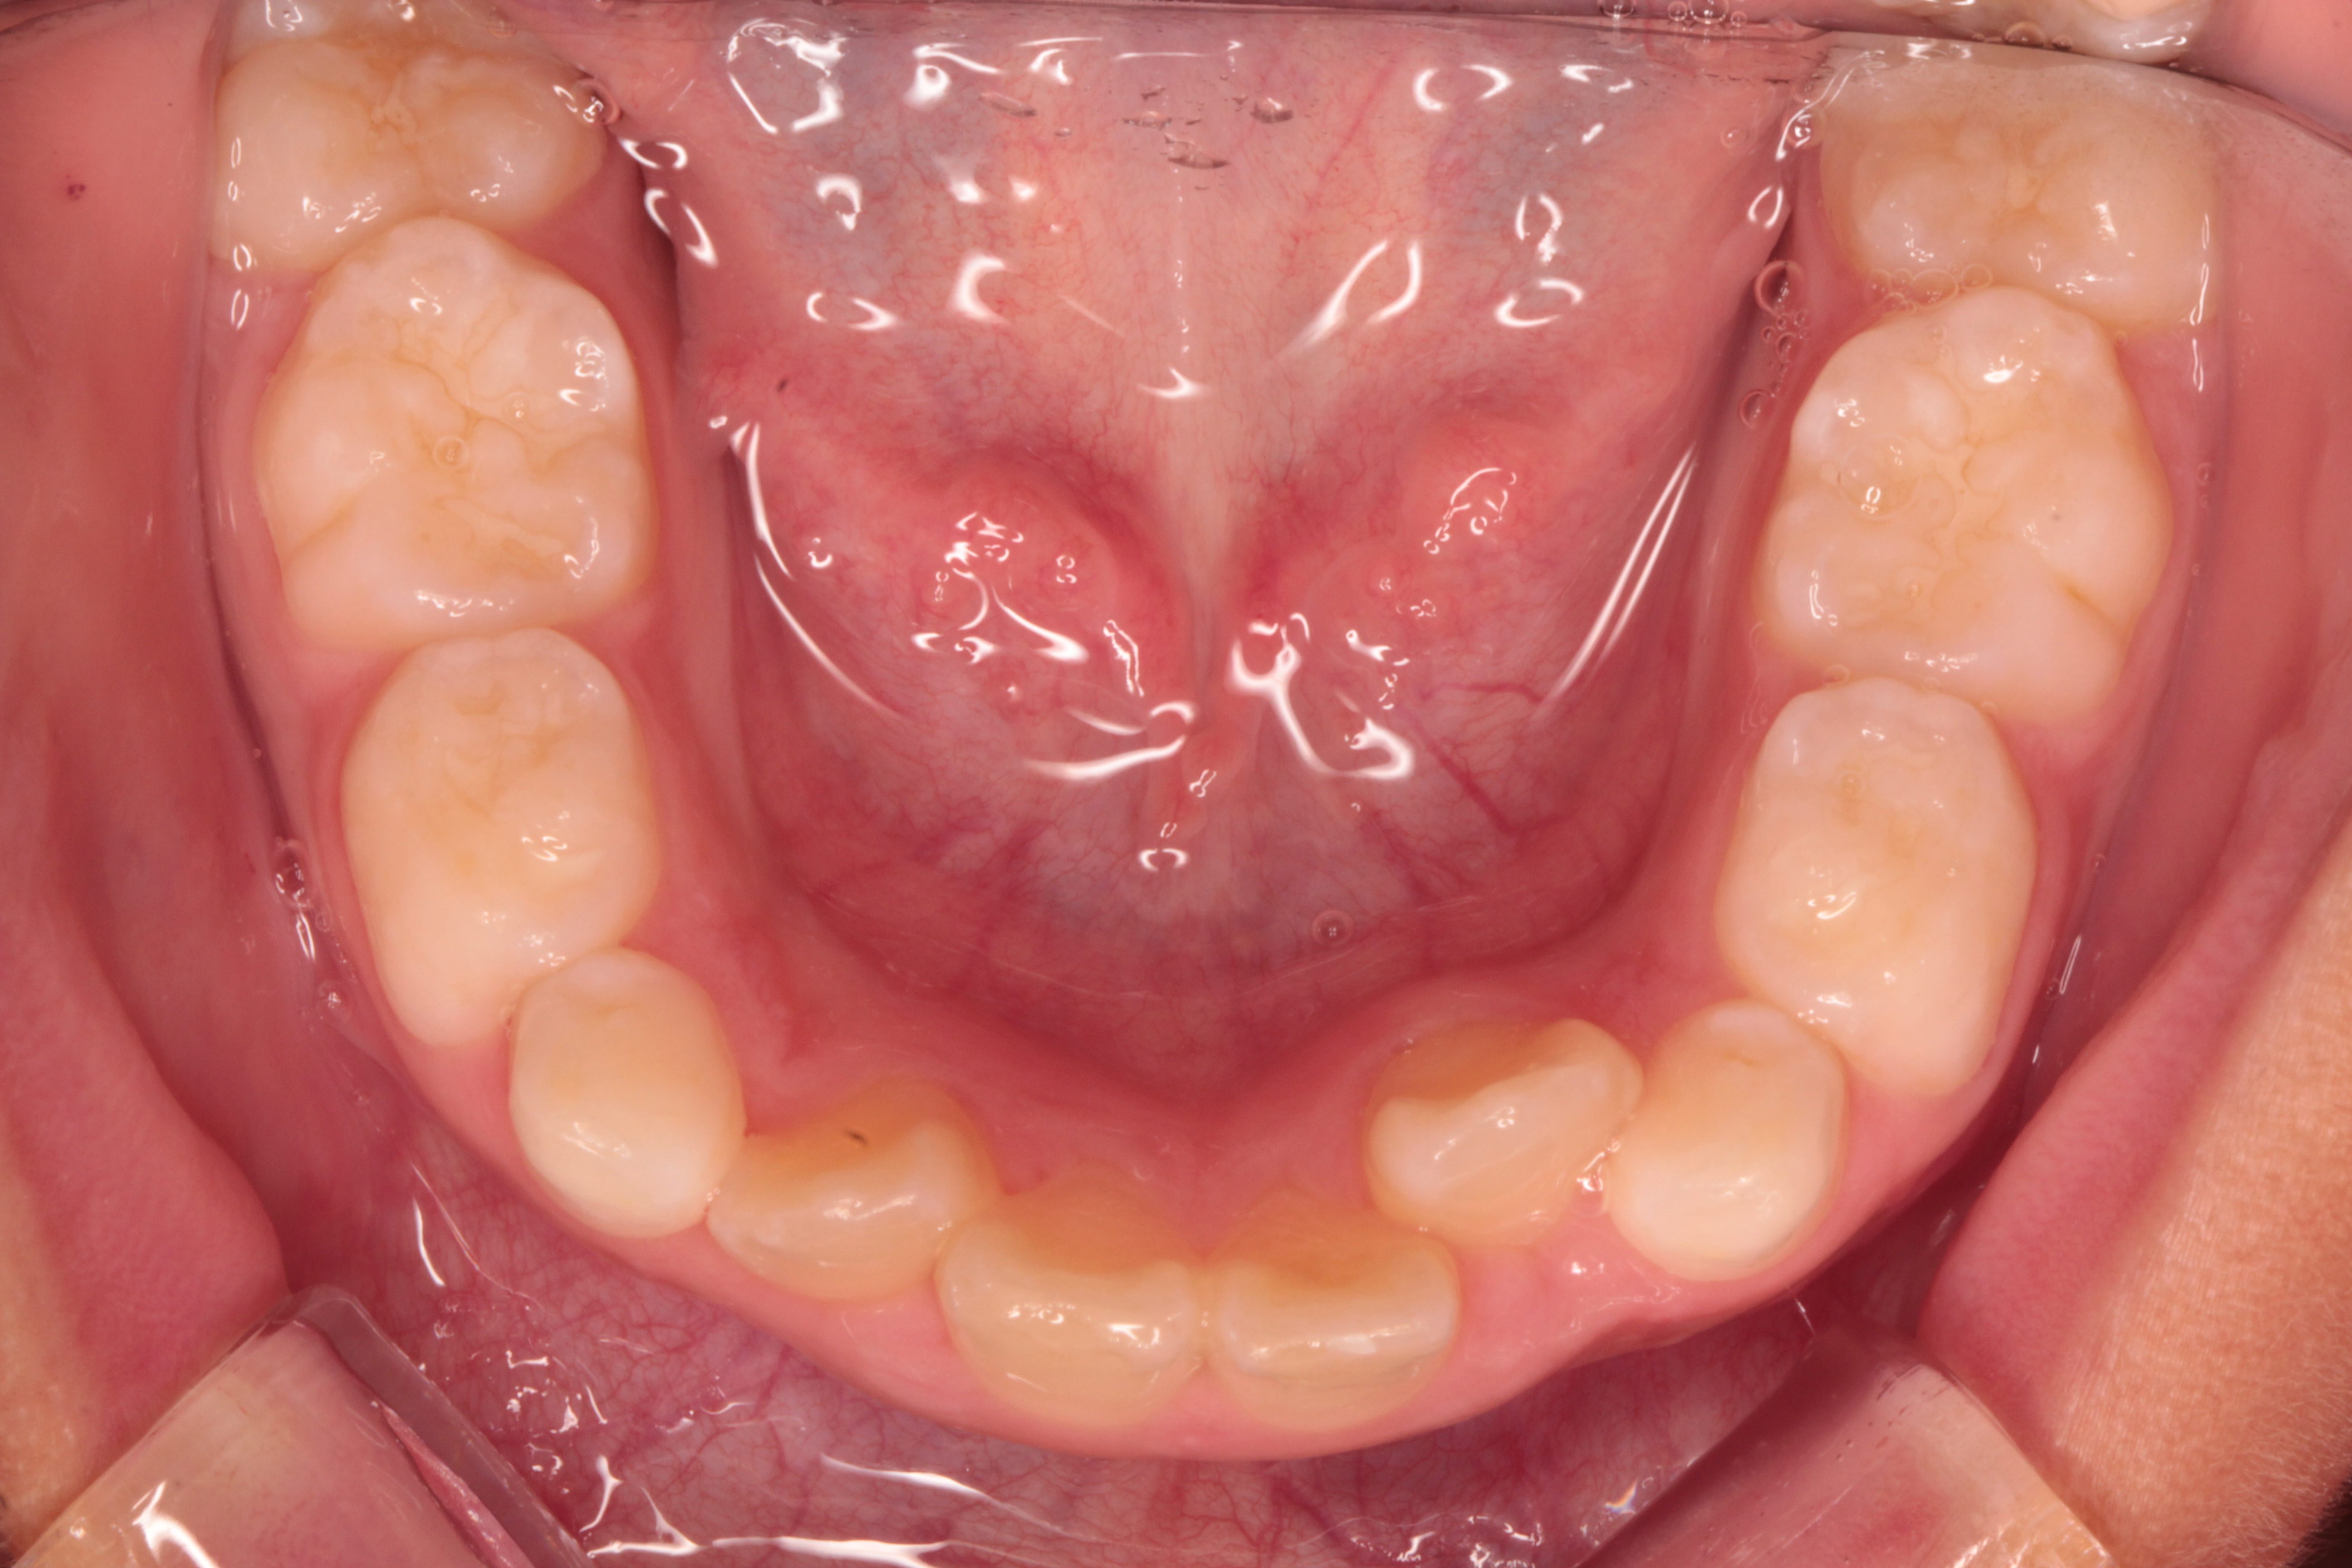

乳歯からの子供(小学生 次男)の歯並び育成

小学校3年生男子で歯並びを主訴としてご来院されました。

ガチャガチャの歯並びの場合、前後左右方向の広がりが小さいばかりではなく、上下的な高さも足りません。

上下的な高さを変えずに歯を並べようとすると、上下とも前広がってしまい、カラス天狗の様になってしまいます。

被せ物で高さを作りました。歯は一切削っておりません。

上下的に高さを作ったところでワイヤーを着けて広げていきます。

約1.5年後です。